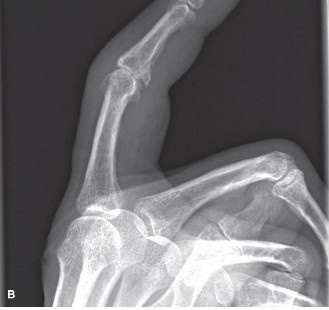

Image

Figure 1: Radiographic presentation of erosive osteoarthritis of the PIP joint, demonstrating classic "gull-wing" deformity with central erosion and peripheral osteophytes.